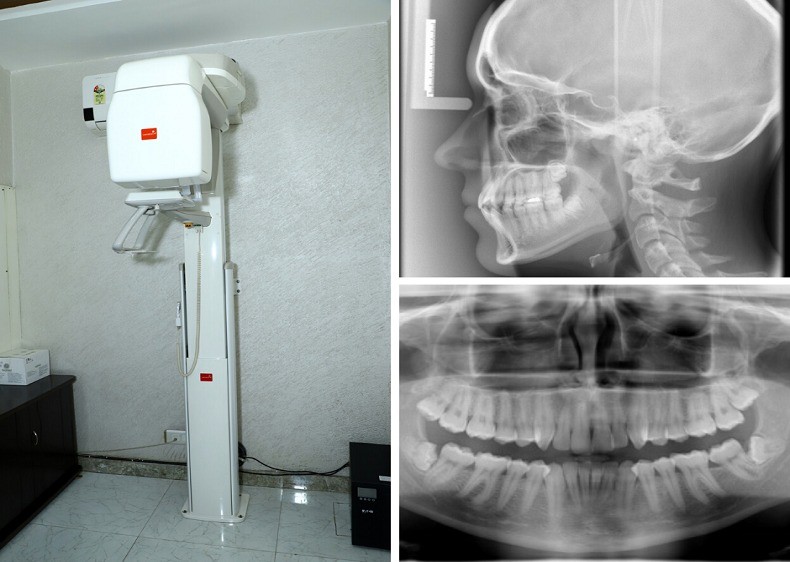

We use high-resolution digital machines that ensure safe imaging and accurate reports. Whether you need a general X-ray or a detailed OPG X-ray in South Delhi, our technology offers crisp, reliable results.

An OPG (Orthopantomogram) X-ray is a panoramic dental X-ray that captures the entire mouth in a single image, including all teeth, upper and lower jaw, and surrounding bone structures. It is commonly recommended by dentists and orthodontists for:

Safe and Comfortable Environment

We ensure that every patient feels comfortable during the procedure. The imaging room is sanitized regularly, and technicians take all necessary steps to ensure minimal discomfort. For OPG X-rays, we use special equipment that requires you to stand still for only a few seconds while the machine rotates around your jaw.